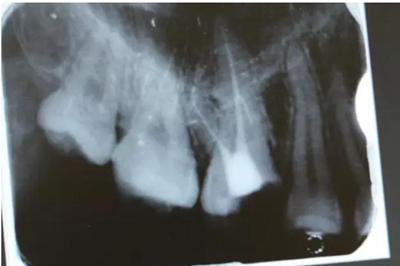

病例一 女性,20歲,大學生,要求補牙,檢查口內(nèi)可見A6大面積缺損,近中牙齦息肉,拍X片,根管充填物略差,但根周未見明顯陰影,口內(nèi)檢查無叩痛。建議患者冠延長手術+高嵌體修復。

患牙遠中邊緣嵴完整,強度沒有降低,故擬保留遠中邊緣嵴,高嵌體修復。首先去除腐質(zhì)及原墊底材料,流體樹脂+3M Z350XT樹脂墊底。局麻下行冠延長手術。在此需要提及個人的一個觀點。冠延長手術原則上要求3-6個月以上才能永久修復。但是個人喜歡后牙肩臺建立在齦上,所以修復后的修復體邊緣位于牙齦上方1mm,對牙周的愈合影響較?。ㄈ绻麨辇l下邊緣則要慎重),故該患者術中按照齦上邊緣的設計進行冠延長手術。以下為術中: